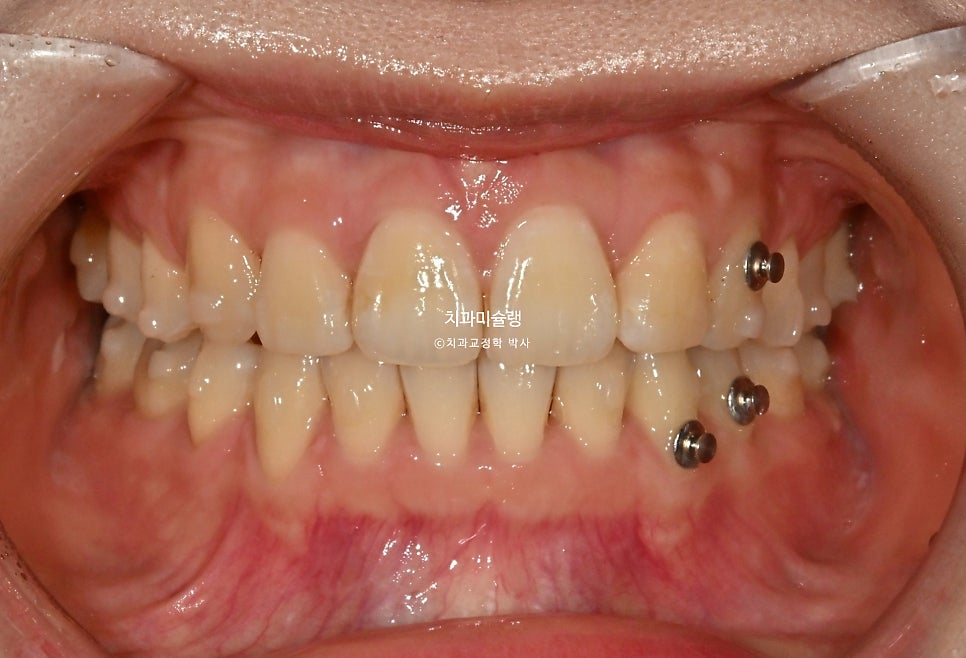

초진 시 구강 상태

앞니 돌출 때문에 입이 편하게 안다물어지는 입술부전증이 경미하게 있습니다.

입안을 보면 앞니가 뻗쳐있는 전형적인 돌출 입니다.

위아래 둘다 중절치가 특히 돌출되어 있습니다.

어쨎든 두번째 세트에서는 앞니 교합이 깊어짐을 방지하고 어금니 쓰러짐을 방지하고자 교정용 나사를 심고 뺏다꼈다 하는 고무줄 처방도 나갔습니다.